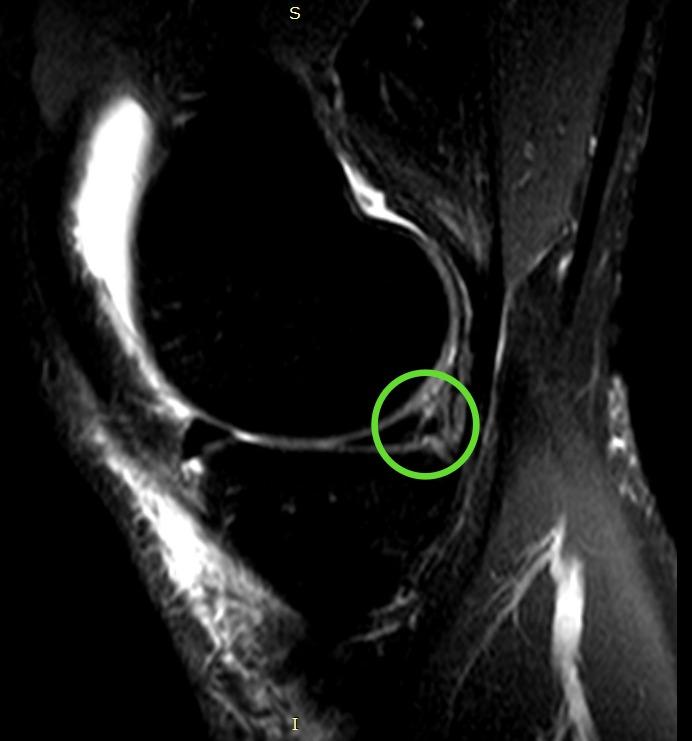

Субтотальный разрыв передней крестообразной связки, частичное повреждение медиальной коллатеральной связки и структур латерального коллатерального комплекса, околокапсулярный разрыв заднего рога медиального мениска.

По итогам исследования и определения диагноза пациенту был предложен и реализован план лечения: предоперационная реабилитация и проведение операции по поводу наложения артроскопического шва заднего рога медиального мениска, а также проведена пластика передней крестообразной связки сухожилием полусухожильной и тонкой мышц правого коленного сустава.